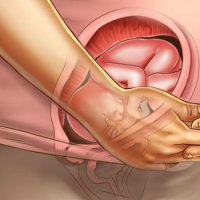

Деякі лікарі можуть переворот дитини провести вручну, зробити так званий зовнішній поворот, якщо жінка молода і здорова. Це означає, що їй не більше 30 років, вагітність настала не в результаті ЕКЗ або ІКСІ, ширина таза, кількість навколоплідних вод і вага в нормі, немає проявів пізнього токсикозу, загрози передчасних пологів та інших важких ускладнень вагітності, а плід відчуває себе добре і не оповита пуповиною. Тоді жінці в стаціонарних умовах внутрішньовенно вводять препарати, повністю знімають напругу матки, після чого лікар рухом двох рук повертає дитини. У разі успішної процедури на вагітну надаватися бандаж.

Даний акушерський прийом заборонений в ряді європейських країн через високий ризик ускладнень і нестійкого результату (нерідко дитина знову приймає неправильне положення через кілька годин / доби після повороту). Подібні дії лікаря можуть призвести до розриву матки, відшарування нормально розташованої плаценти і інших тяжких наслідків. Тому фахівці вважають за краще не ризикувати з зовнішнім поворотом, а проводять пологи при сідничному передлежанні плода шляхом операції кесарів розтин. Як показує лікарська практика і статистика, це найбезпечніше і для матері, і для дитини. Гомеопатія, голковколювання та інші нетрадиційні способи повернути дитину в нормальне положення належного ефекту не показали.